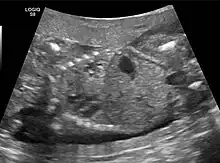

Congenital pulmonary airway malformation in a fetus, ultrasound at 19 weeks -sagittal. Stomach top right of image, heart displaced to bottom left of image (anatomically on the right side of fetus.)

Congenital pulmonary airway malformation in a fetus, ultrasound at 19 weeks - transverse. Stomach on left image; heart on right image: displaced to right by cystic mass

The earliest point at which a CPAM can be detected is by prenatal ultrasound. The classic description is of an echogenic lung mass that gradually disappears over subsequent ultrasounds. The disappearance is due to the malformation becoming filled with fluid over the course of the gestation, allowing the ultrasound waves to penetrate it more easily and rendering it invisible on sonographic imaging. When a CPAM is rapidly growing, either solid or with a dominant cyst, they have a higher incidence of developing venous outflow obstruction, cardiac failure and ultimately hydrops fetalis. If hydrops is not present, the fetus has a 95% chance of survival. When hydrops is present, risk of fetal demise is much greater without in utero surgery to correct the pathophysiology. The greatest period of growth is during the end of the second trimester, between 20 and 26 weeks.